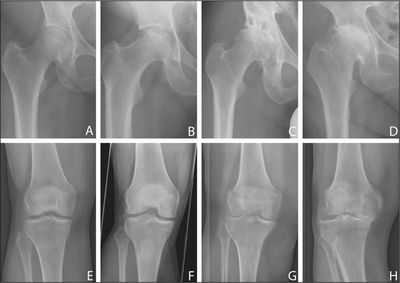

Дегенеративные изменения коленного и тазобедренного суставов.

Скопление жидкости.